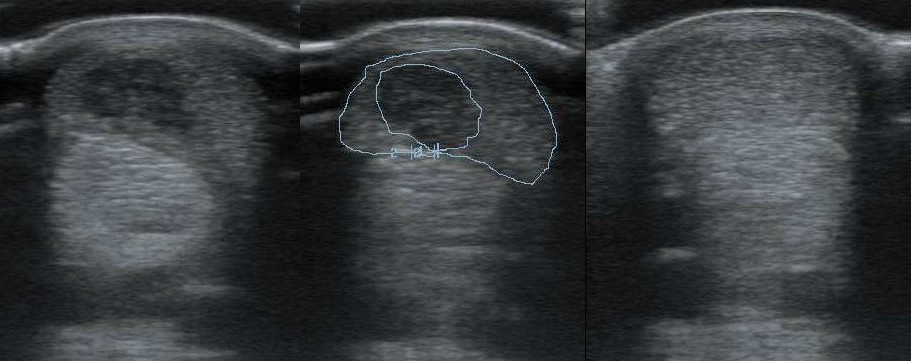

A bal oldali képen egy friss, felületes ujjhajlító ín sérülés látható. A középső képen bejelölve a sérülés, ami 33%-os, kifejezetten nagy defekt. A jobb oldali képen két hónappal az őssejt beadás után a sérülés egyáltalán nem látható!